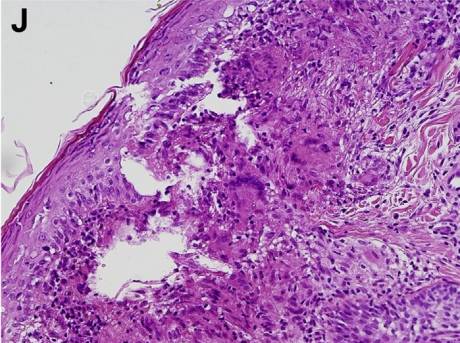

除了消化道病灶活检,还在患者前额皮肤斑点样病灶取活检,结果依然显示:上皮细胞肉芽肿病变(图J)。